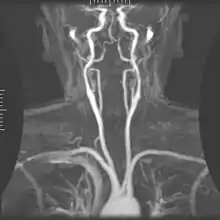

دو سرخرگ کاروتید مشترک (به انگلیسی: Common carotid artery) راست و چپ وجود دارد. به صورت عمومی سرخرگ کاروتید مشترک راست از سرخرگ براکیوسفالیک و سرخرگ کاروتید مشترک چپ از قوس آئورت جدا می شوند.

هر سرخرگ کاروتید مشترک به دو سرخرگ کاروتید داخلی و خارجی تقسیم می شود که سرخرگ کاروتید درونی باعث خونرسانی به نواحی پیشین مغز میگردد. نامهای دیگر سرخرگ کاروتید مشترک عبارتند از خوابرگ مشترک و شریان سُبات مشترک.

خاستگاه و کالبدشناسی

مبدأ سرخرگهای کاروتید مشترک راست و چپ یکسان نیست. سرخرگ کاروتید مشترک راست از سرخرگ بازوییسری[1] یا بی نام (تنه براکیوسفالیک) منشعب میگردد. سرخرگ بازوییسری قطورترین شاخه قوس آئورت[2] است و در پشت مفصل جناغیچنبری (استرنوکلاویکولار) راست به دو شاخه سرخرگ کاروتید مشترک راست و سرخرگ زیرترقوهای[3] راست تقسیم میگردد. سرخرگ کاروتید مشترک چپ و سرخرگ زیرترقوهای چپ بهطور مستقیم از قوس آئورت جدا میگردند. سرخرگ کاروتید مشترک چپ از ناحیه مفصل جناغیچنبری چپ به طرف گردن صعود میکند.

سرخرگهای کاروتید مشترک راست و چپ در ناحیه گردن به دو شاخه انتهایی تقسیم میشوند:

- سرخرگ کاروتید درونی که شاخهای در گردن ندارد

- سرخرگ کاروتید بیرونی